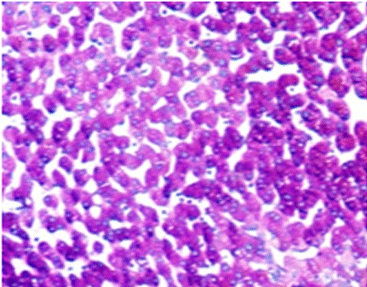

Después de la tinción, la presentación del color de las mucinas ácidas sulfatadas varía desde el marrón violáceo hasta el marrón negro. Las mucinas de los ácidos carboxilados aparecen de color azul. El núcleo celular permanece sin teñir.

10X